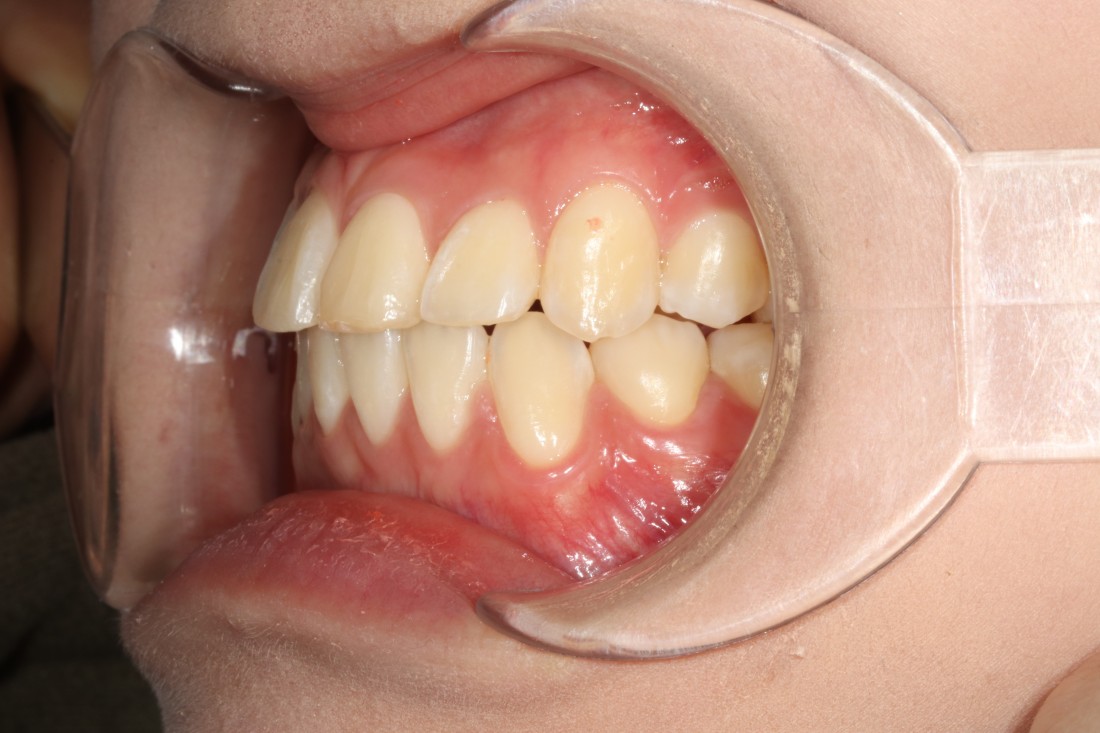

수완동 치아교정 기간은

치아의 이동속도에 따라

예상기간보다 짧아질 수도,

혹은 길어질 수도 있는데요.

월 3만원~5만원 사이의

월 진료비용이 발생하게 되면

몇 개월만 기간이 길어져도

수 십만원의 비용부담으로 다가오기 때문에

수완동 교정치과에서는

월 진료비를 포함하여

추가 금액 결제 없이

합리적인 가격으로

수완동 치아교정을 진행하고 있습니다.